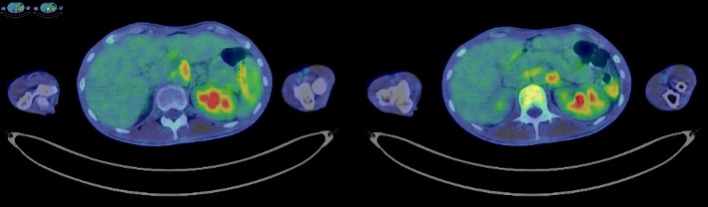

A 23-year-old man was diagnosed with Crohn's disease (CD) of the large intestine after colonoscopy revealed longitudinal ulcers, and pathology revealed non-caseating epithelioid cell granulomas and anal fistulas. The CD relapsed, and therefore prednisolone (PSL) and infliximab (IFX) treatment was initiated. The PSL was gradually tapered. Steroid-free remission was maintained with IFX. The patient subsequently developed a high fever and headache, while CD-related symptoms did not worsen. Laboratory data showed white blood cells at 14,200/µL and C-reactive protein at 17.2 mg/dL. Contrast-enhanced computed tomography revealed thoracoabdominal aortitis, and the patient was consequently diagnosed with Takayasu's arteritis (TA). We therefore again initiated PSL treatment that immediately reduced the fever and headache. The PSL dose was again tapered and the administration of IFX was resumed to maintain CD remission. No further episodes of aortitis relapse were noted after restarting IFX, and the CD currently remains in remission. This is a rare case of TA onset during IFX treatment for CD, and, as such, contributes to the limited literature on such cases. More specifically, this case highlights that when patients with CD present with symptoms such as fever or headache, it is necessary to investigate the possibility of vasculitis.

Abstract Image